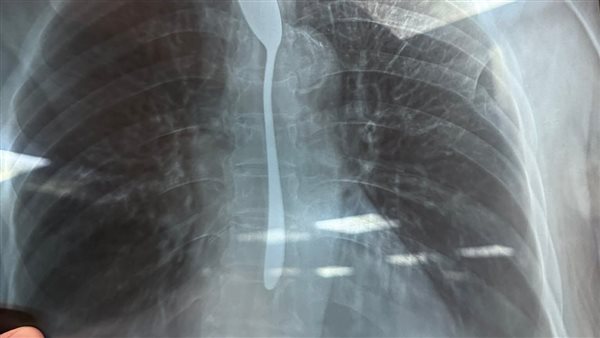

تمكن فريق طبى بمستشفى شبين الكوم التعليمي في محافظة المنوفية، من استخراج ملعقة شاي من معدة سيدة تبلغ من العمر 77 عامًا بعدما ابتلعتها في واقعة تُعد الأولى من نوعها داخل المستشفى التعليمي.

وعلى الفور باشر الفريق الطبي الفحص السريع وإجراء الأشعة اللازمة، ثم نجح في استخراج المعلقة باستخدام منظار طبي دون مضاعفات، وسط متابعة دقيقة للحالة حتى تحسنت وسمح لها بالخروج في اليوم نفسه، بعد أن رافقها سبعة من أفراد أسرتها.